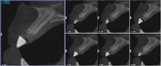

The patient returned at 4 months postoperatively for site evaluation (Figure 11). Bone sounding with an anesthetic needle indicated formation of hard bony surface. At 4 months lamellar bone is present.7 A cone-beam computed tomography (CBCT) scan of site No. 8 radiographically confirmed that the bony ridge had been regenerated (Figure 12). CBCT measurements indicated the maxillary ridge was 6.44 mm wide and 21 mm tall.

Fig 12. CBCT at 4 months postoperative showed vertical bone regeneration.

Figure 12